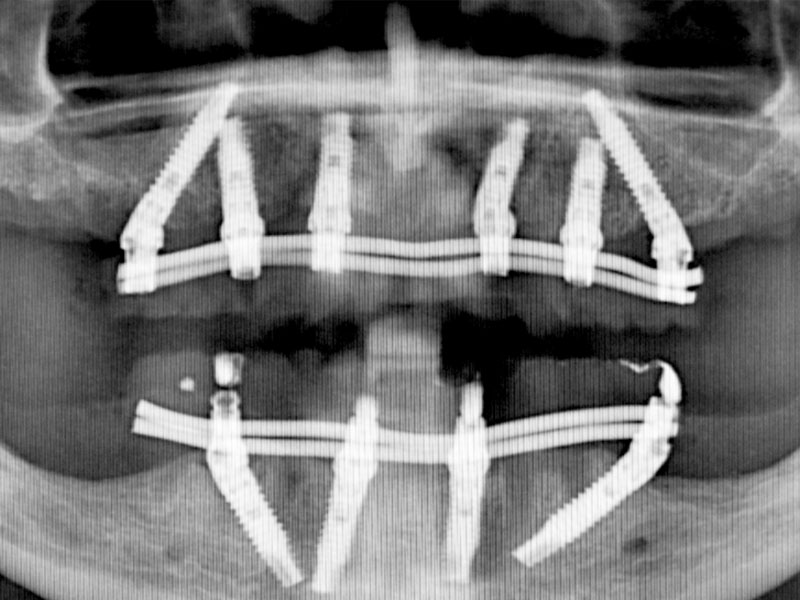

ALL ON 4 下顎 / ALL ON 6 上顎